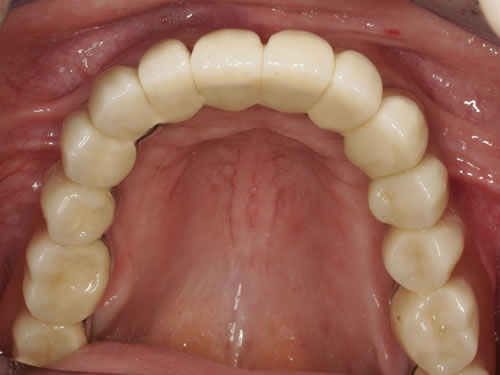

Auch eine festsitzende zementierte oder verschraubte Brücke ist möglich (Abb. 8.17 bis 8.19). Hierbei muss eine günstige Lachlinie vorliegen und der Kieferschwund sollte noch nicht zu weit fortgeschritten sein. Die Zähne würden sonst sehr lang wirken, da die Zahnpositionen in die ehemalige Position der Zähne zurückgebracht werden muss. Langes Prothesentragen und entsprechender Knochenverlust erschweren besonders im Oberkiefer festsitzenden Zahnersatz. Sehr exakte Voruntersuchungen und präzise Implantatpositionen mit entsprechenden Knochenaufbaumaßnahmen sind häufig notwendig, um den Patienten diesen Wunsch zu erfüllen.

Abb. 8.18: Verschraubte Brücke auf Implantaten im zahnlosen Oberkiefer (Frontalansicht).

Abb. 8.19: Zufriedene Patientin nach Eingliederung des neuen Zahnersatzes (Lachlinie).